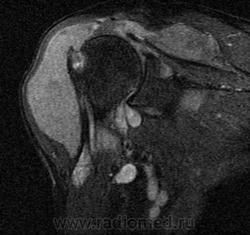

Пигментный виллёзонодулярный синовит - редкое заболевание с доброкачественным течением, характеризующееся пролиферативными изменениями синовиальной оболочки, отложением гемосидерина, образованием ворсинок, паннуса. Две разновидности: виллёзонодулярный бурсит и виллёзонодулярный тендосиновит. Частота - 2 на I 000 000. Преобладающий возраст • Виллёзонодулярный бурсит - 30-40 лет • Виллёзонодулярный тендосиновит -50-60 лет. Преобладающий пол - женский. Этиология. В 30% случаев развитию синовита предшествует травма сустава. Патоморфология. Пролиферация клеток синовиальных оболочек с образованием узлов, содержащих клеточный инфильтрат из фибробластов, лимфоцитов, макрофагов с жировыми включениями. Клиническая картина • Виллёзонодулярный бурсит -моноартрит. Чаще всего (80% случаев) поражается коленный сустав, реже - (с убывающей частотой) тазобедренный, голеностопный и плечевой суставы • Виллёзонодулярный тендосиновит - образование узелков в мышечных сухожилиях и связках сустава. Лабораторные исследования • Увеличение СОЭ • Синовиальная жидкость ксантохромная, с примесью крови • Биопсия синовиальной оболочки: узловая пролиферация, гемосидероз, инфильтрация мононуклеарными клетками. Рентгенологическое исследование • Остеопороз и наличие остеофитов нехарактерны • Артропневмография: множественные округлые дефекты наполнения синовиальной полости, обусловленные наличием узлов или гипертрофированных ворсинок синовиальной оболочки • МРТ - выявление гемосидерина и жировых включений. Артроскопия • Суставной хрящ приобретает коричневую окраску вследствие гемосидероза • Различной величины узлы коричневого цвета. Дифференциальный диагноз • Виллёзонодулярный бурсит • Липома - в аспиратах отсутствует ксантохромная жидкость • Остеоартроз - кисты возникают только на суставных поверхностях, подвергающихся нагрузке, тогда как при пигментном виллёзонодулярном синовите они образуются на всех суставных поверхностях. Остеофи-ты, напротив, более типичны для остеоартроза • Воспалительные арт-ропатии, дебютирующие моноартритом, - ревматоидный артрит, туберкулёзный артрит, анкилозирующий спондилоартрит и др. • Виллёзонодулярный тендосиновит - панглии (околосухожильные кисты): аспираты ганглиев содержат гелеподобную жидкость. Лечение хирургическое • Виллёзонодулярный бурсит • Тотальное иссечение синовиальной оболочки, вероятность рецидива заболевания составляет 25-40% • Лучевая терапия • Виллёзонодулярный тендосиновит - иссечение кист. Синоним. Синовит геморрагический МКБ. М12.2 Ворсинчато-узелковый (виллонодулярный) синовит (пигментный)

Мальчик 10 лет, не так давно перенесший незначительную травму правого коленного сустава. На рентгенограмме костные структуры целостные, лишь определяется выраженное расширение и минимальное усиление мягких тканей.  На первом представленном изображении определяется выраженное скопление жижкостного содержимого. Синовиальная оболочка утолщена с гипоинтенсивными участками.

Аксиальная томограмма Т1 после усиления Gd с жироподавлением демонстрирует диффузные и узелковые синовиальные разрастания. Очаги накопления указаны стрелками в синовиальной оболочке и в жировом тельце Гоффа.